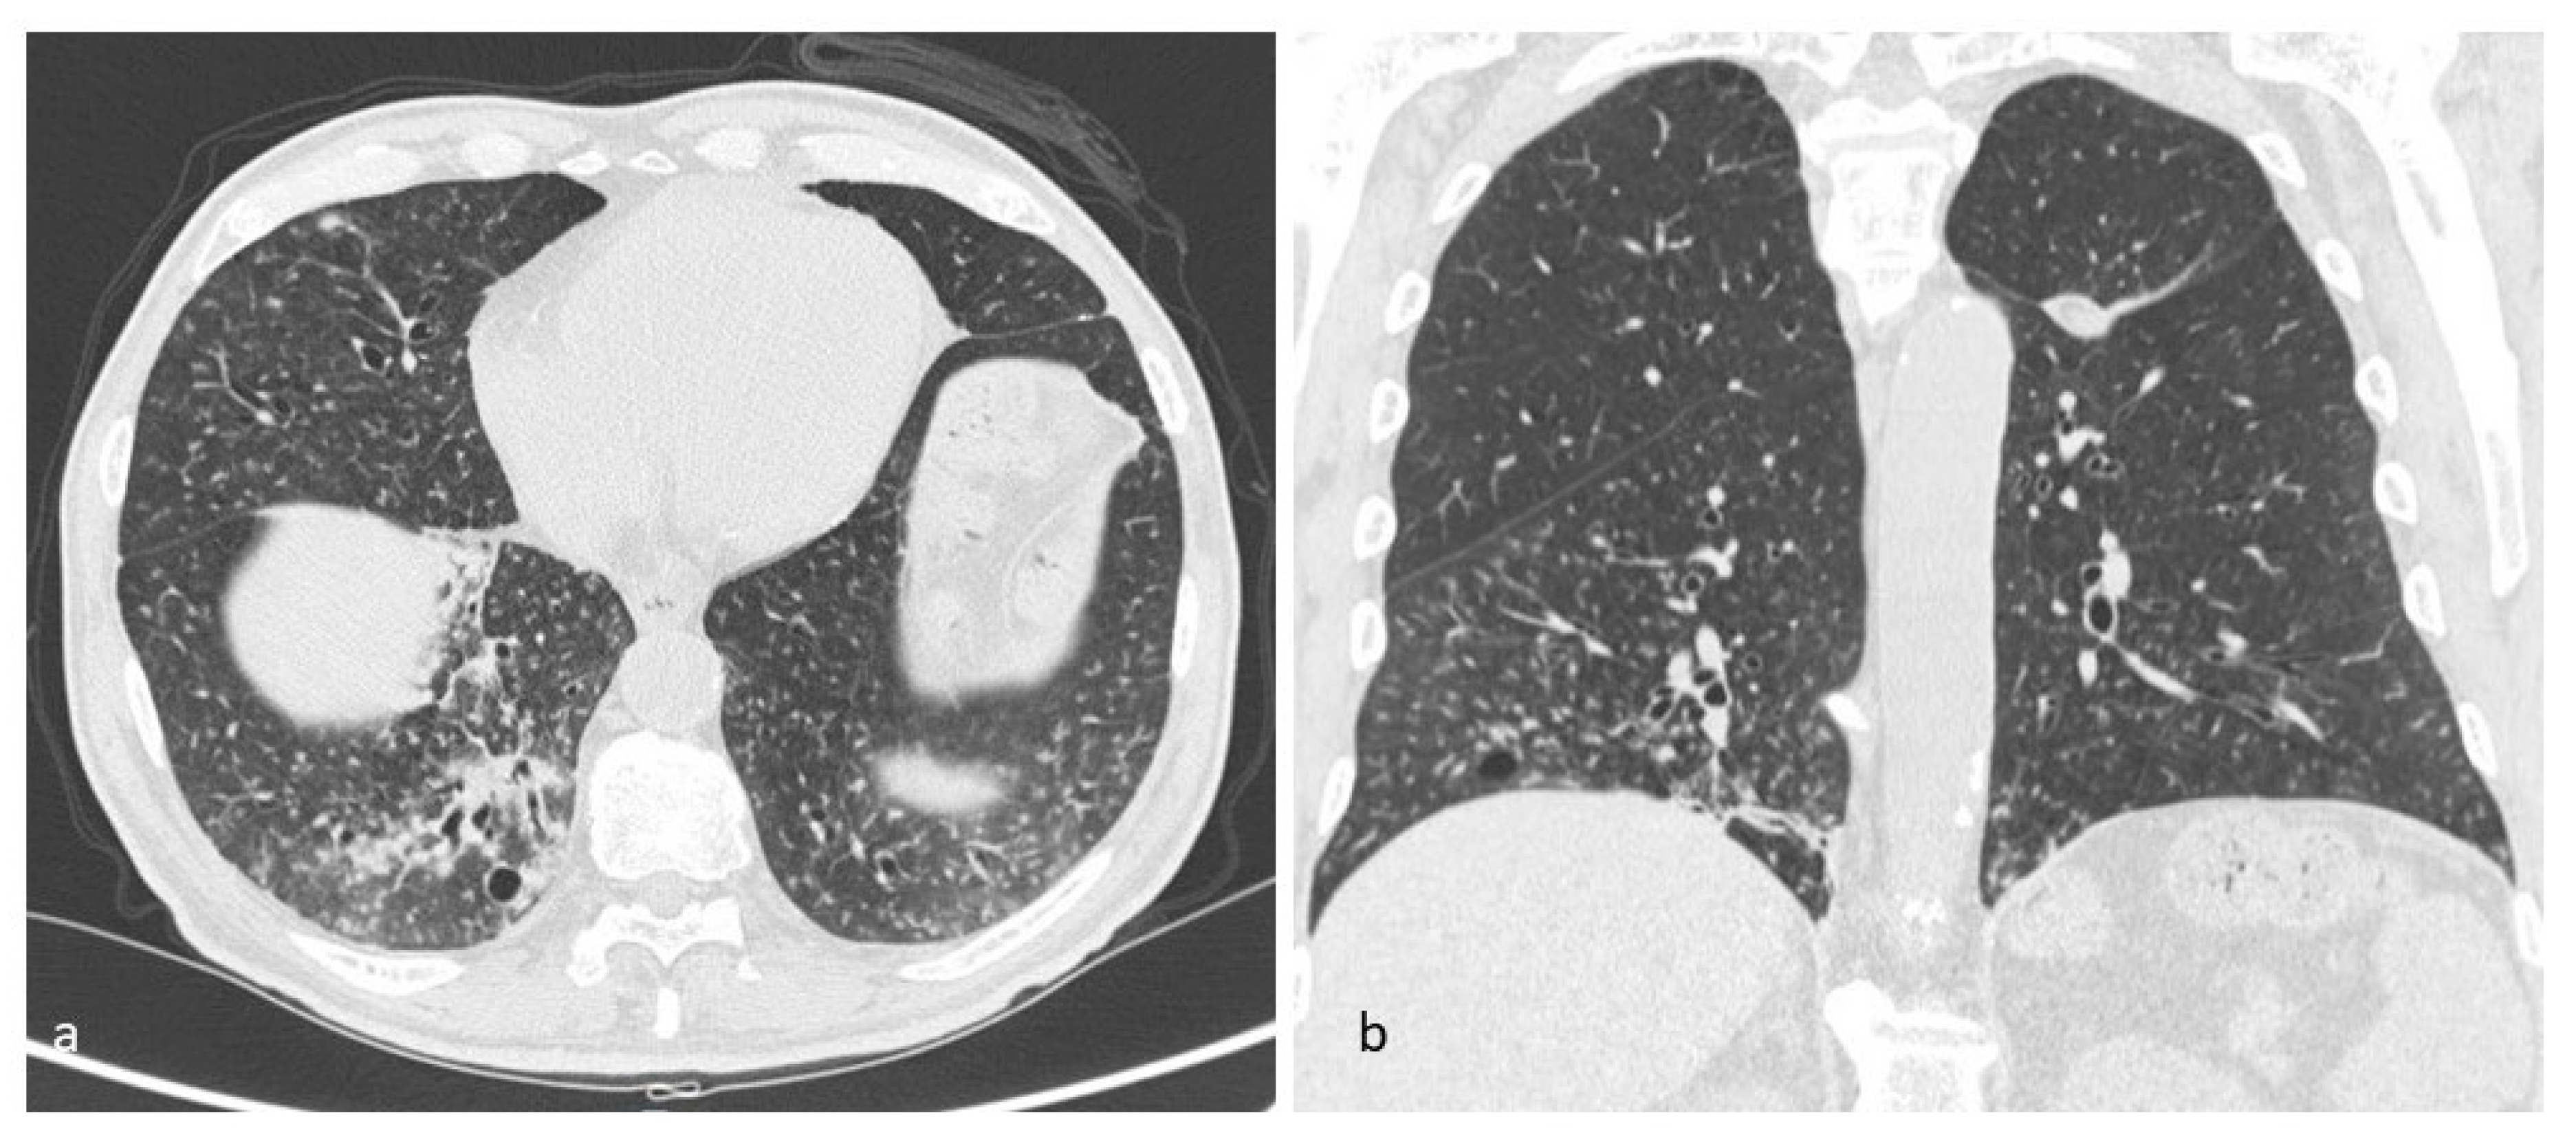

Figure 3. LCH cystic pattern, with multiple cysts predominantly located in the upper lobes (a,b) and in the apical segments of the lower lobes (c), with typical sparing of costophrenic angles (d). On multiplanar reconstructions (MPR) in the coronal (e) and sagittal (f,g) plane is evident the typical distribution of lesions. This figure has been partially modified from ECR 2017/C-2141 Cystic pattern in lung diseases: a simplified HRCT guide based on free-hand drawings, DC Caltabiano, V. Costanzo, L. Mammino, V. Vindigni, S. Torrisi, R. Rosso, LA Mauro, C. Vancheri, S. Palmucci.

Lung cysts, which are the most advanced expression of the evolution of LCH, may vary in size from one to several centimeters; they occur with thick wall and “bizarre” morphology, having poli-lobulated or clover-leaf contours, in contrast to the more uniform and bland cysts typical of other diffuse cystic lung diseases, such as LAM; the cysts have also a wide distribution (Figure 2), with a predominance in the lung apices and the medium regions, typically sparing costophrenic angles (Figure 3); this distribution is one of the diagnostic keys that distinguishes LCH from LAM [10] (Figure 4). Another helpful clue is the sparing of the medial tips of medial lobe and lingula; lung volumes are normal or increased, an unusual appearance when reticular opacities or honeycombing occur. Frequently, cysts are the only alteration found in HRCT scans, but in most cases small nodules are also detectable.